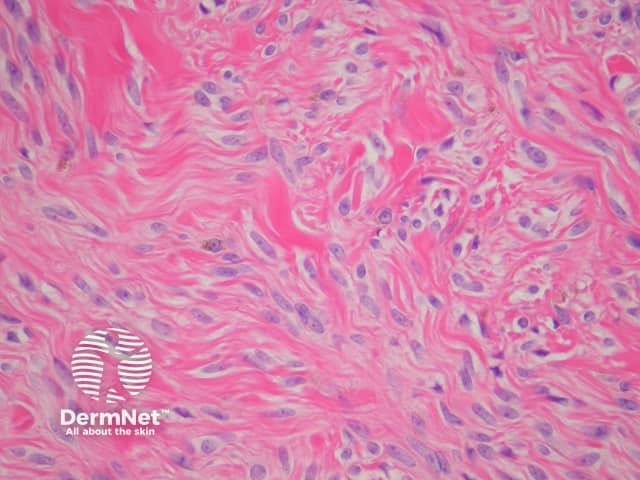

Histopathologically, blue naevi have a collection of dendritic melanocytes in the dermis (figure 2). Pure common blue naevi should not involve the epidermis. The connective tissue surrounding the melanocytes is usually sclerotic, sometimes profoundly so, when it is described as a sclerotic blue naevus. Aggregation of melanocytes about appendages and neurovascular bundles is common. Melanophages are usually also present in large numbers, which partially explains the blue clinical presentation.

Figure 2